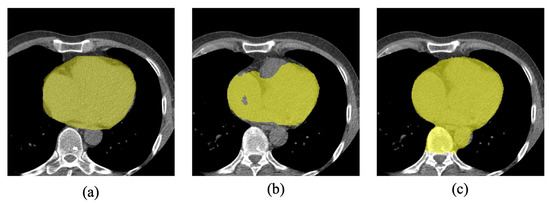

2. Data and Methods

2.1. Data Set-Up